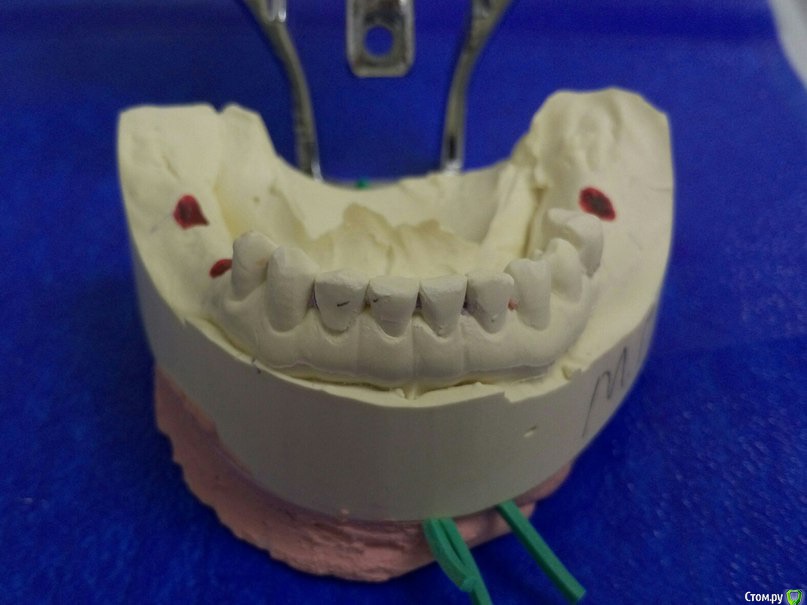

Доброго времени суток коллеги, сразу извиняюсь за качество фото т.к. фотографировал на тапок. Вот такая ситуэшн, на днях ко мне попала пациент от коллеги с окклюдатором в руках, где загипсованы модели в привычном прикусе. Там где отмечены красные точки, стоят уже формирователи. Сделал оптг, забрал модели.

На сегодня имеем феномен Попова-Годона в области 1.6, 1,7, стираемость нижних резцов, глубокое резцовое перекрытие. Думаю, что все это связано с длительным отсутствием жевательных зубов.

4. Оттиски с имлантов для изготовления временных коронок винтовой фиксации в новом соотношение челюстей.

По снимку явно дегенеративные изменения сустава, бугорка почти нет, поэтому я думаю можно было бы, для начала попытаться поднять высоту на имплантах используя временные абатменты и времянки. Сможете поднять прикус на необходимую высоту + частично попытаться устранить феномен попова-годона (если зубы оставлять), за одно понаблюдаете, как на это отреагирует сустав. На мой взгляд при таком состоянии сустава даже с лицевой дугой будет проблематично идеальное определение ЦС ИМХО. Все остальное на времянках думаю до года. И на ОПТГ надо было сережки снять :rolleyes:  ;) . Можно сразу уменьшить высоту 1.6,1.7, учитывая карман глубокий за 1.7, а можно все их убрать (1.9,1.8,1.7,1.6) и поставить импланты(меньше геморроя) :)